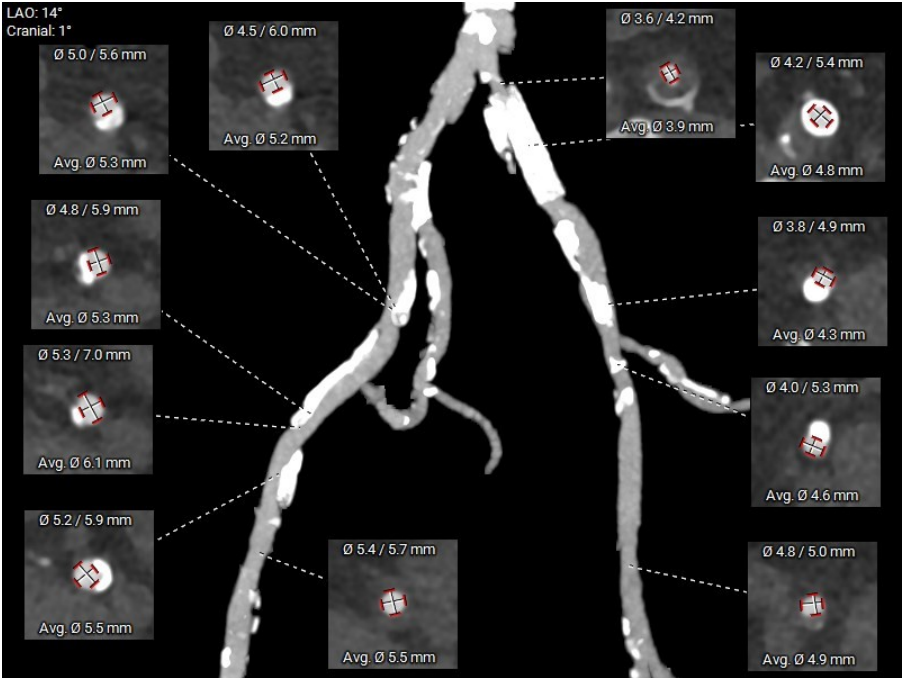

CT评估-外周测量:双侧入路偏细,左侧入路小于5.0mm,右侧髂外段入路最小约5.3mm,见三段长条钙化,考虑输送系统通过难度极大;锐角弓约64°,弓部到髂股动脉钙化较多,股动脉分叉皆位于股骨头以下